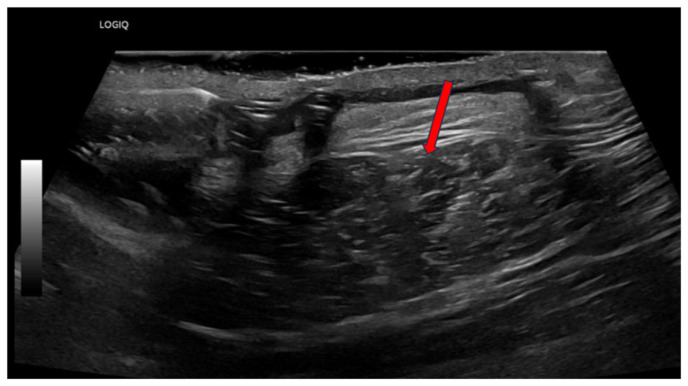

Implantable cardiac devices, including cardiac pacemakers, are not without risk for infection, carrying a mortality and morbidity of around 5-15%. Gram positive organisms are most common in 91% of cases, whereas gram negative organisms are less common, found in 2% of cases secondary to gram negative organisms other than Pseudomonas aeruginosa. Here, we present a rare case of the gram-negative organism Proteus mirabilis leading to a pacemaker site infection.